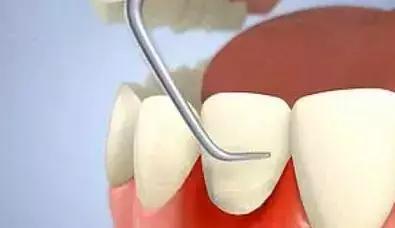

(2).龈下牙石:位于龈缘以下、龈袋或牙周袋内的根面上,肉眼不能直视,必须用探针探查,方能知其沉积部位和沉积量。龈下牙石中无机盐的主要来源是龈沟液。 牙石对牙周组织的危害,主要是构成了菌斑附着和细菌滋生的良好环境。

1.牙周袋形成:由于炎症的扩展,牙周膜被破坏,牙槽骨逐渐吸收,牙龈与牙根分离,使龈沟加深而形成牙周袋。可用探针测牙周袋深度。